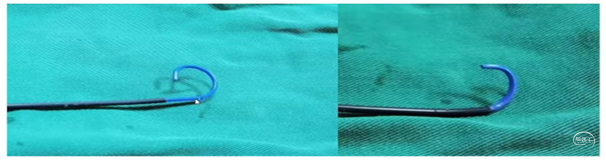

2、可选择对侧桡动脉置入6F动脉鞘,单弯或西蒙导管将0.035泥鳅导丝置于病灶侧锁骨下动脉起到牵拉作用。

3、将6F导引导管到达狭窄椎动脉附近,微导丝导引球囊扩张支架(4-5mm)铆定狭窄部位后扩张释放支架。

备注:6F导引导管可兼容0.035 in泥鳅导丝和球囊扩张支架(4-5mm),5mm支架通过略涩。